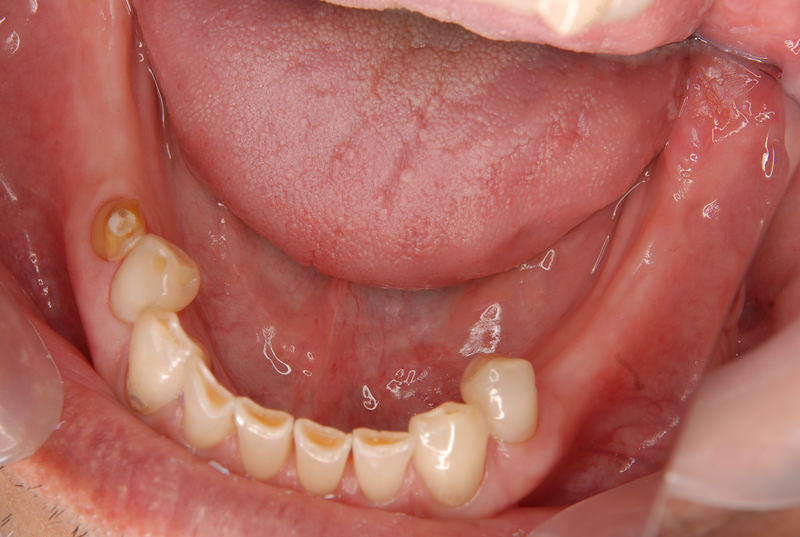

症例140代 男性 主訴 奥歯に歯を入れたい、しっかり噛みたい

治療前

治療後(5年経過)

主訴 奥歯がない為、食事が不自由である。入れ歯は煩わしいので、固定制のインプラントにして欲しいと訴え来院。口腔内全体で6本のインプラントを埋入。仮歯にて神経筋機構、顎関節のバランスを整え、リハビリを経て、約5ヶ月後にジルコニアを装着。

リスクとしては、外科的侵襲がある。デメリットは、保険外診療の為、経済的負担がある。

費用 316万(税込) (オペ・仮歯・最終補綴物まで含む)